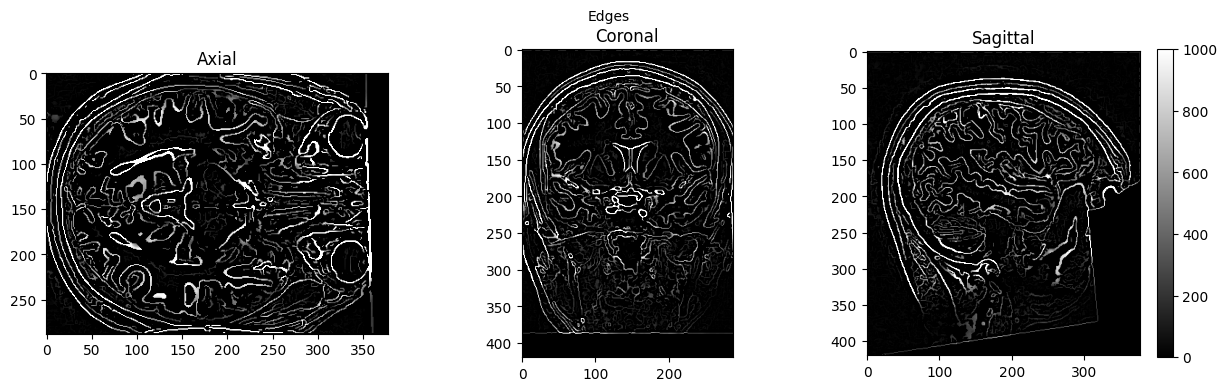

edge3 = afni.Edge3()

edge3.inputs.in_file = './sub-01_ses-01_7T_T1w_defaced.nii'

edge3.inputs.out_file = './sub-01_ses-01_7T_T1w_defaced_edges.nii'

edge3.inputs.datum = 'byte'

res = edge3.run()

view_slices_3d(edges, slice_nbr=230, vmin=0, vmax=1000, title='Edges')